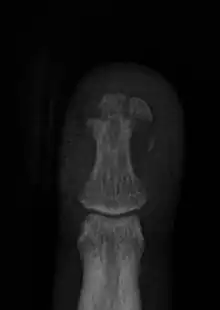

| Dorsal hand injury seen in a child | |